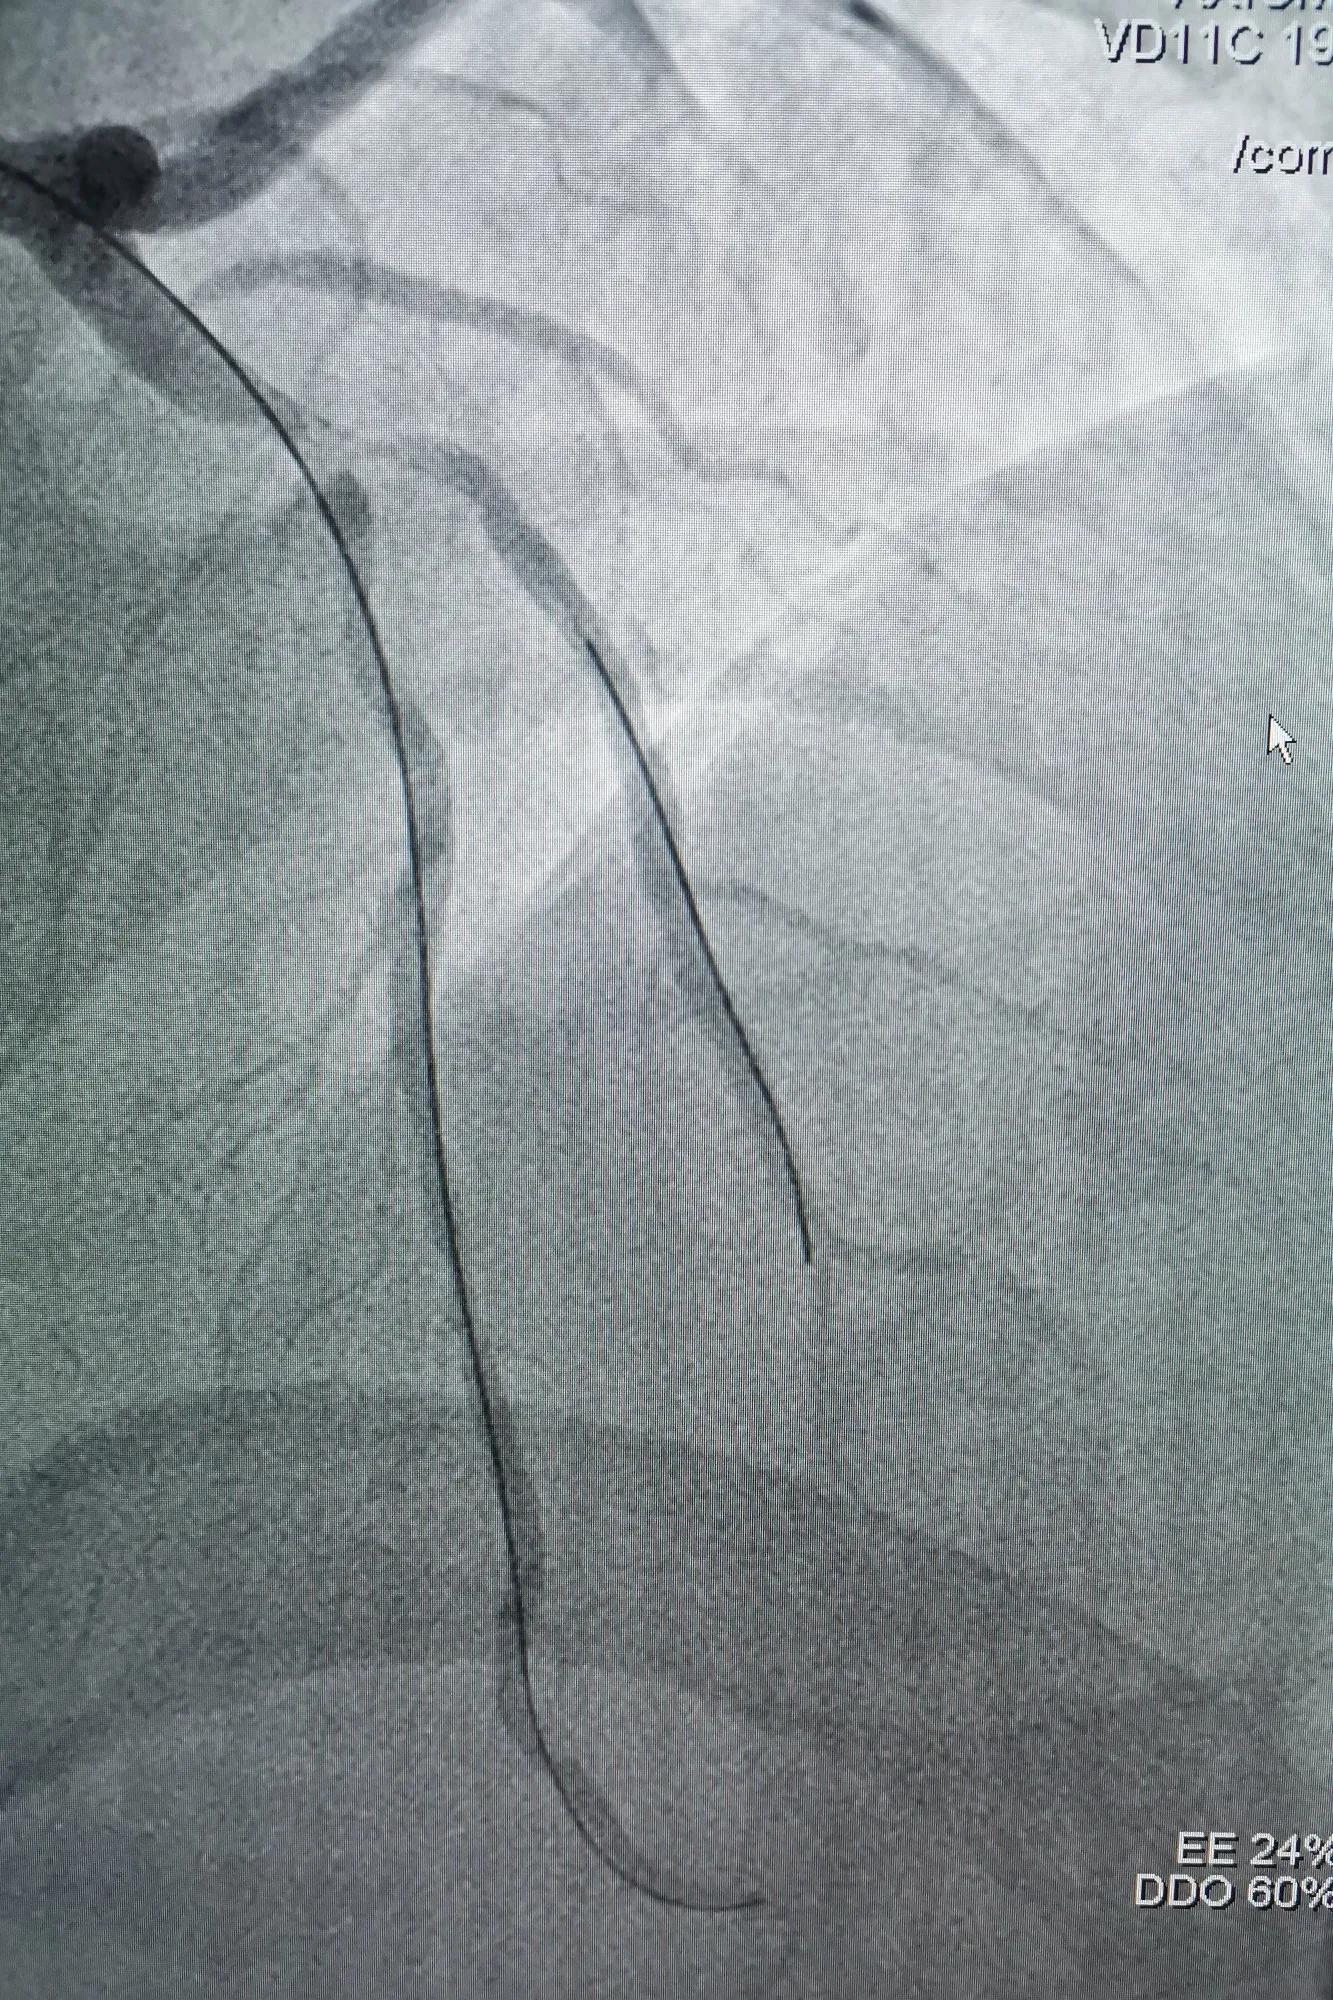

(双导丝球囊扩张LAD近段狭窄病变)

(SION导丝到D1远端保护)